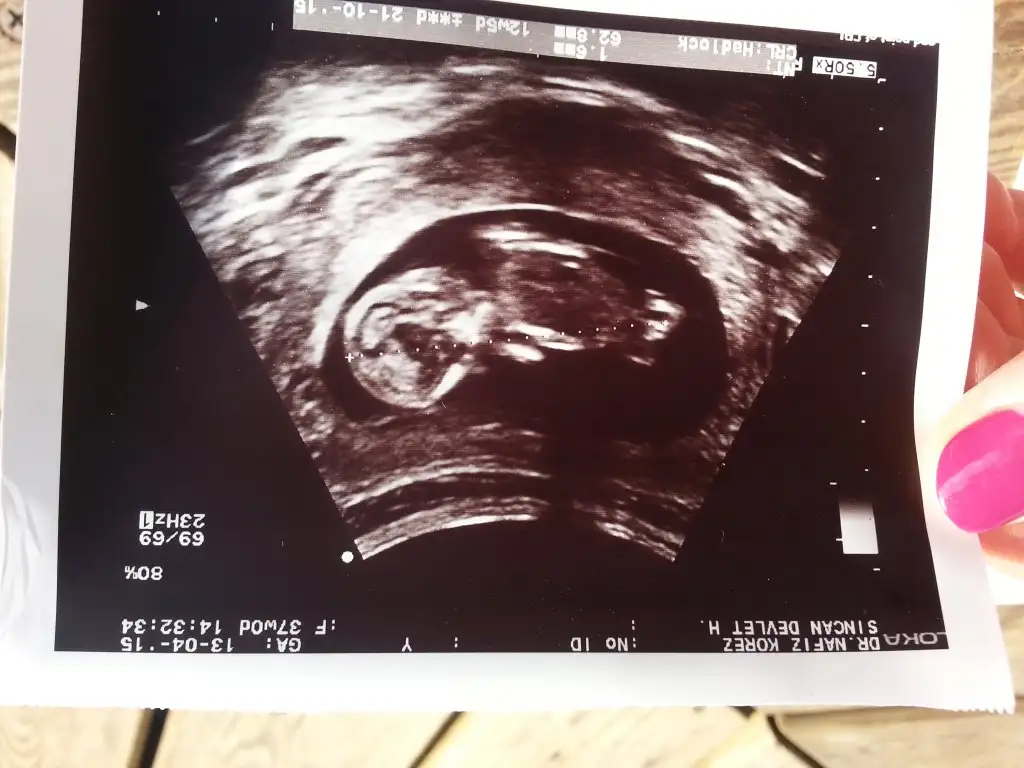

Canim kac haftalik bu bebis vajinal ultrasindan bakilmis ...[/Bu resimde 13 haftalik .gelecek persembe yeni randevum 17 haftalik oldum simdi .belli olmuyor galiba burda dimi ?

cok teşekkürler :) evet 12 haftalık 1 ay sonra belli olur sanırım yazarım :)Buyuk ihtimal kiz gibi.. ne zaman belli olacak..masallah cok sekilliuo bo bebis ama ciokinti hic yokk...kiz bu bebis ogrenince yaz cabim..